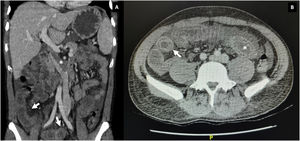

Durante la hospitalización, el día 4 se diagnosticó enteritis lúpica por la presencia de dolor abdominal, diarrea y tomografía de abdomen contrastada con signo de la diana en el íleon distal (fig. 1). Adicionalmente, por episodio de cefalea en trueno (día 7) se realizó angiorresonancia cerebral que detectó trombosis en la confluencia del seno venoso transverso, sigmoideo izquierdo y sagital superior (fig. 2; tabla 1). Por estos hallazgos se inició infusión de inmunoglobulina y anticoagulación.